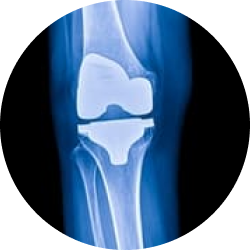

Редрессация коленного сустава нужна в следующих случаях:

- травматическое повреждение связок, мениска;

- разнообразные артрозы;

- патологическая трансформация синовиальной оболочки в хрящевую ткань;

- нестабильность надколенника различной этиологии;

- деформация конечности;

- наличие у пациента кисты Бейкера;

- дегенерация и травматизация хрящей;

- нарушение целостности большой берцовой, бедренной кости, мыщелков;

- хронический воспалительный процесс синовиальной оболочки;

- негативные последствия, которые возникли после эндопротезирования.